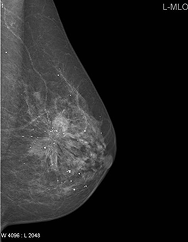

CC Left

Left CC Sample

CC Left Grad-CAM